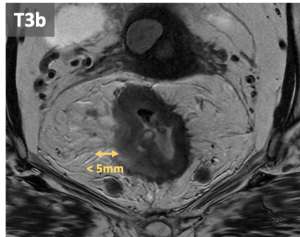

- T3: Tumor extension into the mesorectal fat, beyond muscularis propia. T3 can be subclassified according to the extramural invasion depth:

- T3b: 1-5 mm